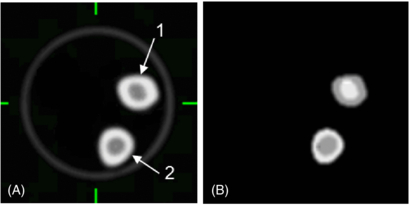

We performed a single scan of three frozen bovine femur segments positioned in a 20 × 20 cm2 cylindrical phantom. The phantom also contained a 5 cm diameter cylinder with dilute iodine-based contrast agent as a reference. A 10 min 2D PET transmission scan was acquired on a GE Advance PET Scanner (GE Healthcare, Waukesha, WI) and reconstructed with the FBP algorithm with a 5 mm Hanning window, obtaining a set of 65 4.25 mm thick slices, each 128 × 128 pixels of size 2.3 mm × 2.3 mm. A CT scan of the same phantom was acquired with the GE Discovery STE PET/CT scanner using 140, 120 and 80 kVp with 200 mAs. The attenuation coefficients from CT were calculated from a filtered version of the CT image covering a FOV of 70 cm, yielding a data set of 73 × 3.75 mm image slices, each with 512 × 512 pixels of size 1.37 mm × 1.37 mm. The CT image was then downsampled (with linear interpolation) to match the PET transmission pixel size and both images were aligned manually as shown in figure 2. This final phase of the CT image converted to a PET attenuation map is termed the CTAC image. The accuracy of alignment was visually assessed to be better than 2 mm in all directions. Both the CTAC and TX images represent the spatial distribution of the LACs at 511 keV with units of cm−1.

Figure 2. Axial and sagittal views of frozen bovine femur segments in a 20 × 20 cm2 cylindrical phantom. (A) CTAC image (140 kVp) interpolated to match the PET transmission resolution and after scaling attenuation coefficients to 511 keV using the tri-linear transform (figure 1 and table 1). (B) 10 min PET transmission (TX) image at 511 keV used as a reference standard.

Download figure:

Standard imageFive volumetric regions of the bones were segmented by thresholding and erosion of the CT image to obtain equivalent volume masks for the PET TX and CTAC images. Two regions were from compact bone, two were from cancellous bone and one was from the contrast cylinder. Two of these volume masks are shown in supplemental figure 1 (supplemental materials are available online only, from stacks.iop.org/PMB/57/2477/mmedia). Differences between the average LACs within each region from the two images were then calculated. The numerical results are reported as the per cent error in the average LACs at 511 keV by

In the second experiment, we evaluated the impact of inaccuracies in the CTAC image on the estimated tracer SUV in the corresponding PET image. Due to the difficulty of introducing a known quantity of FDG into the bovine bone, we instead simulated an emission image by thresholding the CT image to determine bone regions and then assigned different activity values to each segmented region (figure 4). The assigned PET tracer uptake values are given in table 2. To simplify the analysis we removed the contrast cylinder and the smaller bone (no. 3) from the bovine phantom images.

Figure 4. Transaxial sections of the CTAC (A) and simulated PET (B) emission images of tracer uptake in bone used to evaluate effect of CTAC errors on PET SUVs measured from bone tissue in the bovine femur phantom.

Download figure:

Standard imageTable 2. Assigned ('true') PET tracer uptake values in the bovine femur phantom for experiment 2.